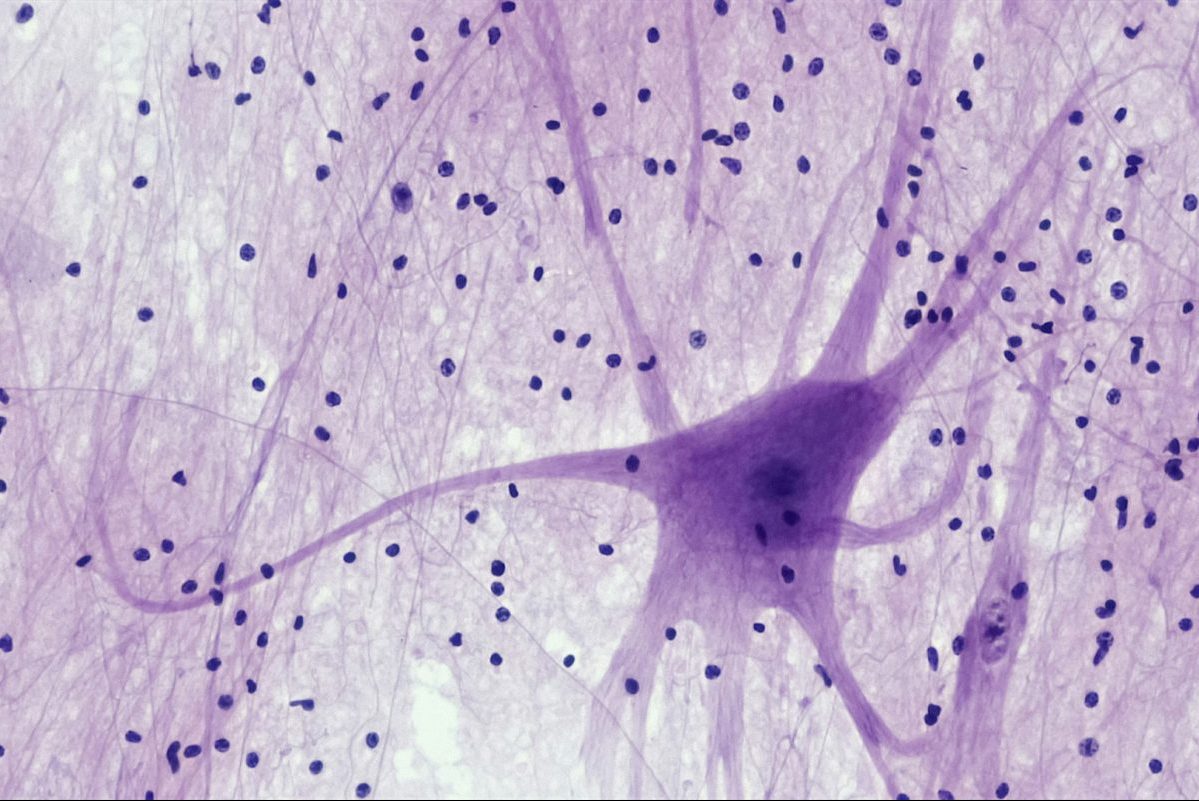

Νευρικό σύστημα

Unsplash Bioscience image library by Fayette Reynolds